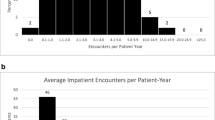

We were able to calculate the age at which CT scans were performed for all in-house scans, this ranged from 0 to 18 years, with a mean age of 6 years old. The highest number of CT scans were however seen in those children aged 0–1 year (Fig. 1). A general trend demonstrating a higher number of CT scans performed in patients who had their shunt inserted at a younger age was observed (p = 0.086), with those children undergoing insertion of shunt prior to 25 months of age being exposed to the highest number of CT scans (Fig. 2). A significant correlation between numbers of CT scans and number of shunt-years was observed (p = < 0.05), with a greater number of CT scans performed in those children who had a shunt in place for a longer period of time (Fig. 3). There appeared to be two populations in this dataset, one in which number of CTs appeared to correlate with shunt-years, and a further population in which no CT scans were performed for the first 5 years after shunting (Fig. 3).